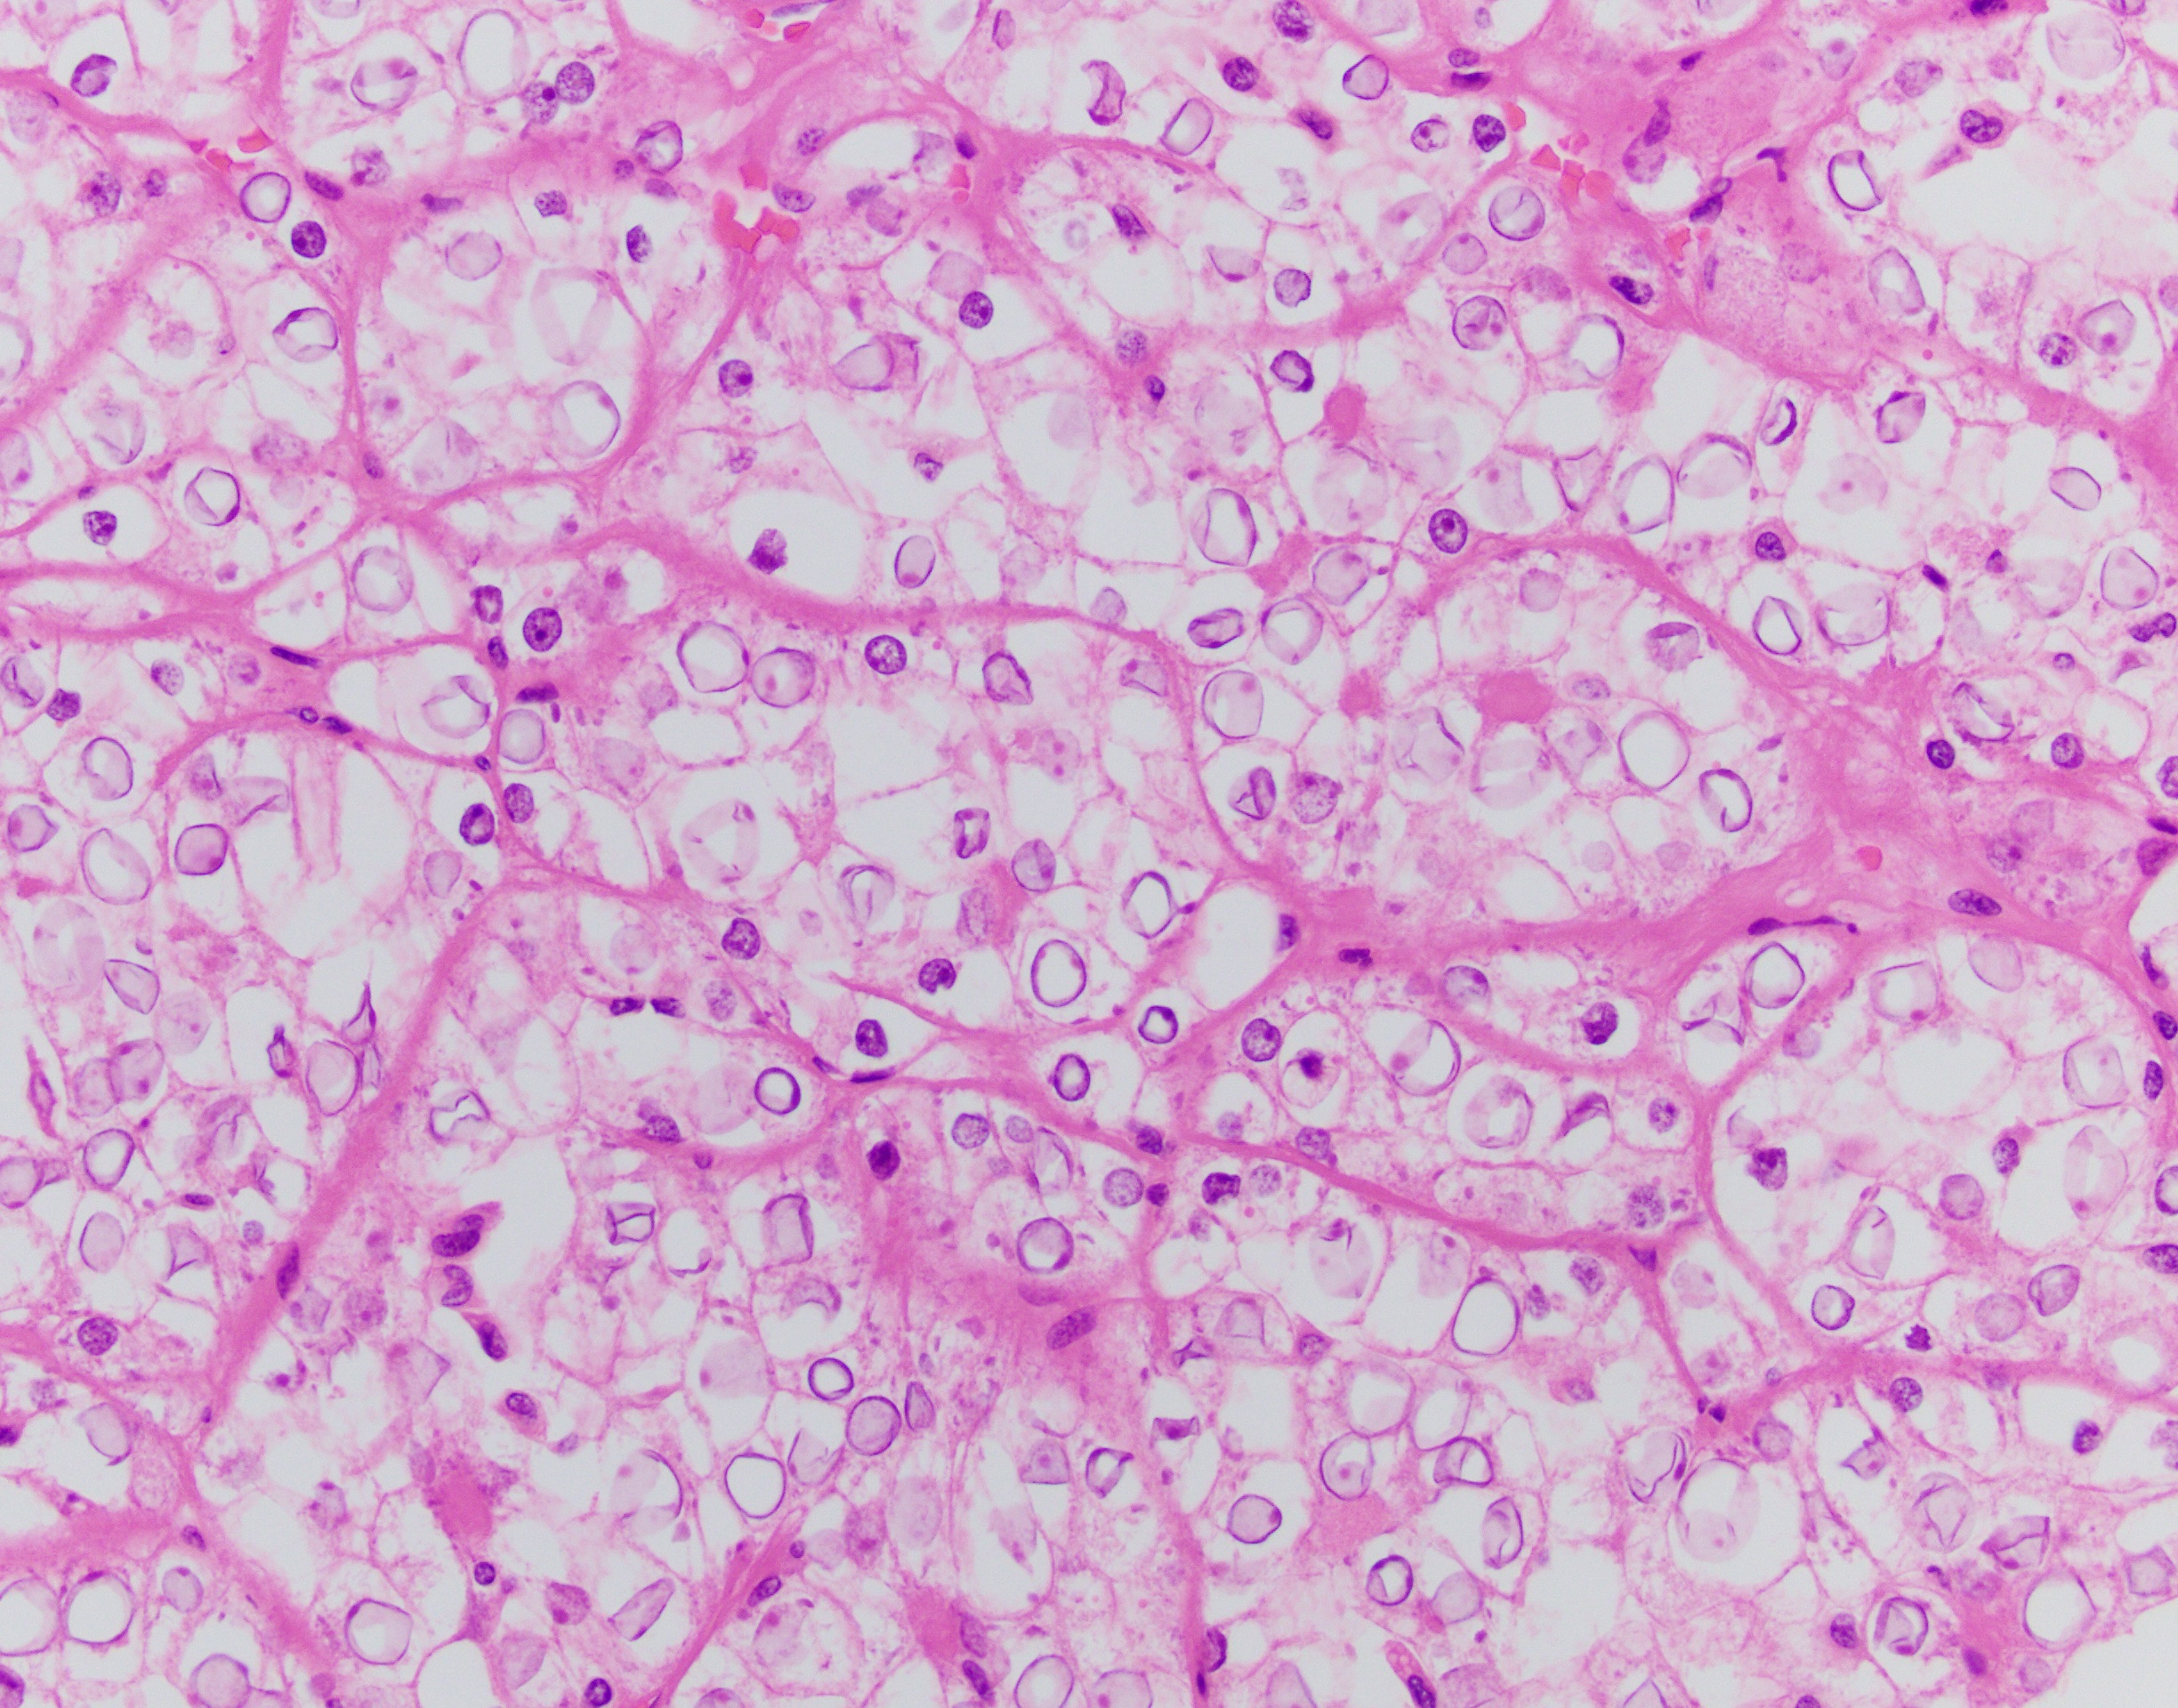

The neoplasm has a compact architectural growth pattern with confluent anastomosing cords, tubules and acini. The tumor cells have granular eosinophilic cytoplasm containing glycogen. The nuclei are round to oval with slightly irregular contours, having a distinct chromatin pattern with condensation at the periphery with clearing of the central portion.

Translocation-associated RCCs involve the MiTF/TFE (Microphthalmia-associated transcription factor/transcription factor binding to IGHM enhancer 3) family genes. The primary genes involved are either TFE3 (located at Xp11.2) or TFEB (located at 6p21.1). Due to the relatively small number of cases studied so far, knowledge of the clinical aspects and outcome of these tumors is not complete. They do represent at least 20% of RCCs in the pediatric age group. Histologically, t(6;11) carcinomas usually consist of nests and microscopic cysts composed of polygonal cells with pale or eosinophilic cytoplasm. Papillae are uncommon. These cells can be arranged around nodules of hyaline material in large acini.